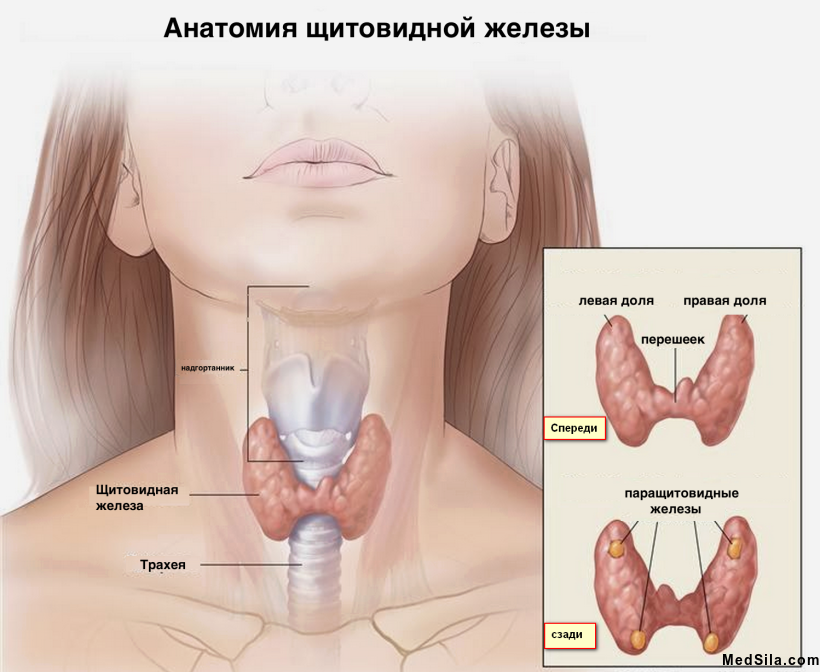

Тиреоидэктомия - это основной и главный метод лечения рака щитовидной железы, заключающийся в полном удалении всей ткани щитовидной железы.

Удалить железу необходимо вместе с прилежащими лимфатическими узлами, дабы полностью избавить организм от атипичных клеток. Ведь в первую очередь рак щитовидной железы дает метастазы (он распространяется) именно в регионарные (рядом лежащие) лимфатические узлы. Поэтому, при подтвержденном раке щитовидной железы, удаляется комплекс в виде щитовидной железы с капсулой и двусторонним удалением лимфоузлов, расположенных возле трахеи и яремной вены.